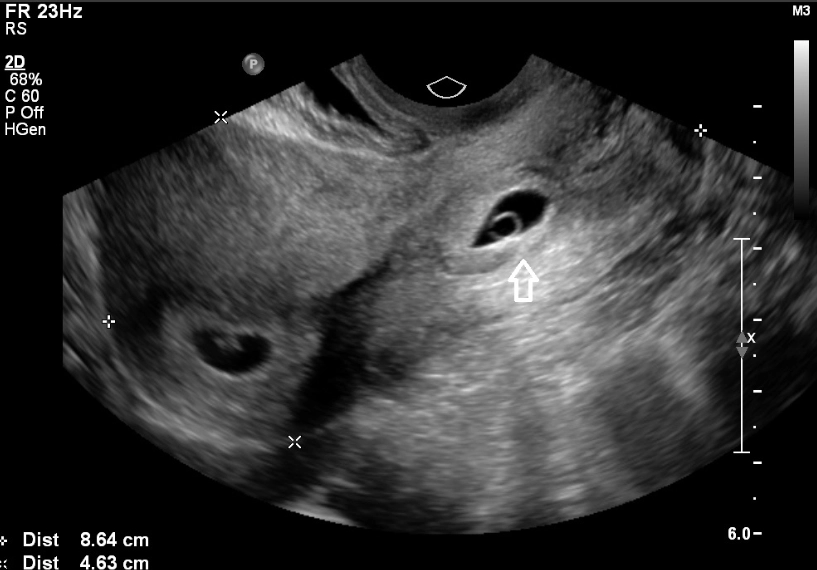

- Subchorionic hematoma: A small bleed between the uterine wall and the placenta. Many resolve on their own.

When to call: For any bleeding, it's wise to check in with your provider's office. They'll likely ask about the color, amount, and if there's pain. They may want to see you for an ultrasound for peace of mind. The American College of Obstetricians and Gynecologists (ACOG) has a helpful resource on bleeding during pregnancy that outlines the different causes.